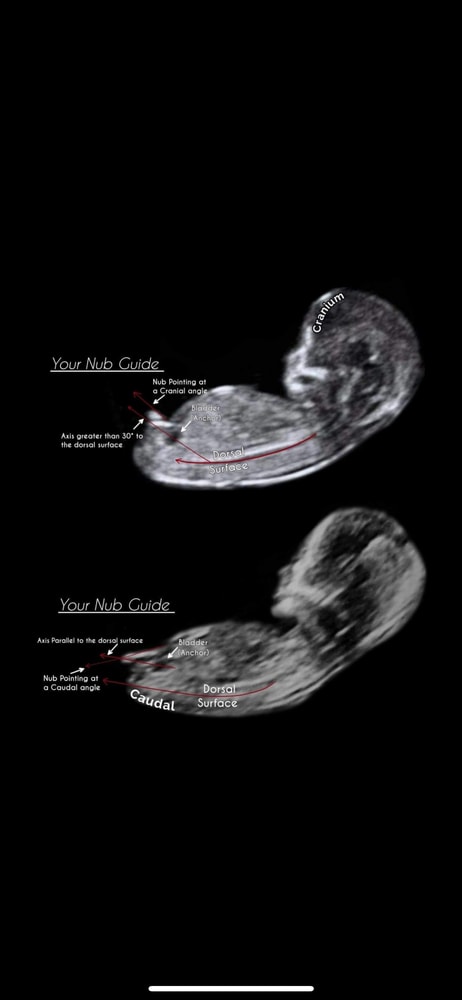

А у нас так же было. Прям точь в точь. У меня сын. Жаль что фото остались на разбитом телефоне и их не восстановить( а у дочери вообще бугорок этот был мизерным, почти не видно). Но это у нас так. Вообще, если вниз смотрит, то скорей всего девочка

Девочка. Параллельно позвоночнику. Без угла